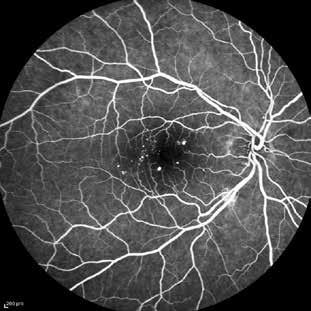

Type 2 MNV refers to the proliferation of new vessels originating from the choroid into the subretinal space. These vessels penetrate through the sub-RPE, making the subretinal portion the dominant component of the pathological process in Type 2 neovascularization. On FA, these lesions are usually “well-defined” as they present a well-demarcated area of hyperfluorescence in the early phase of the angiogram, followed by progressive dye pooling in the overlying subsensory retinal space during the late phase. (Figure 2)

Figure 2. Multimodal imaging of Type 2 macular neovascularization. Infrared reflectance (A) and fundus autofluorescence (B) revealing abnormalities of retinal pigment epithelium. Early and late phase of indocyanine green angiography (C and D) and fluorescein angiography (E and F) showing a well-defined neovascular network. Optical coherence tomography angiography (G) displaying the neovascular network. Optical coherence tomography (H) showing the neovascularization above the retinal pigment epithelium with disorganization of the overlying inner segment/outer segment junction.